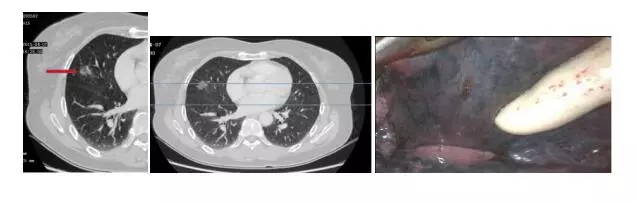

病例2:女性,60岁,体检发现右肺中叶肿物3天。CT:右肺中叶见磨玻璃样密度增高影,边界模糊,大小约1.2x1.2cm,纵隔窗消失。术中快速病理:腺癌。术后病理:(右肺中叶)高分化以贴壁状为主型腺癌,局部伴乳头状成份,未见明确浸润证据,体积约1X1X1cm,未见明确神经及脉管累及,支气管残端未见癌,淋巴结未见癌转移:2,4组0/3,7组0/5,9组0/2,10组0/4,11组0/3,12组0/3,附免疫组化:CK+,TTF-1+,P53少+,Ki67 5%+。